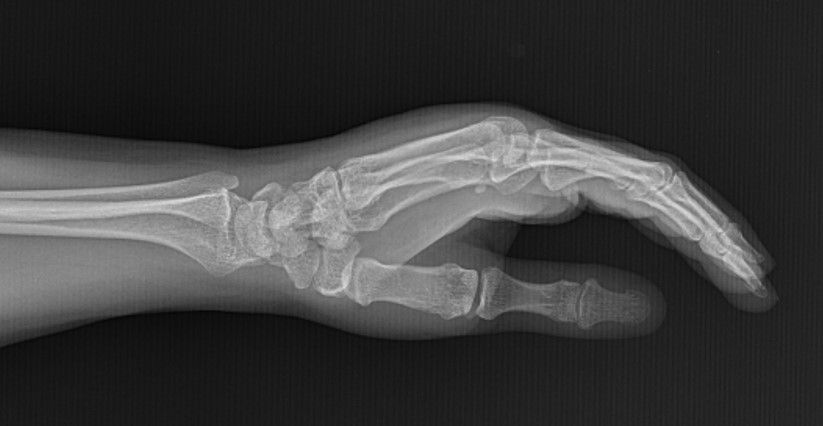

Case 21 - Scaphoid Fracture

45 yr, female, housewife, right hand dominant

Fall on outstreched right hand one month ago.

Treated with thumb spica cast.